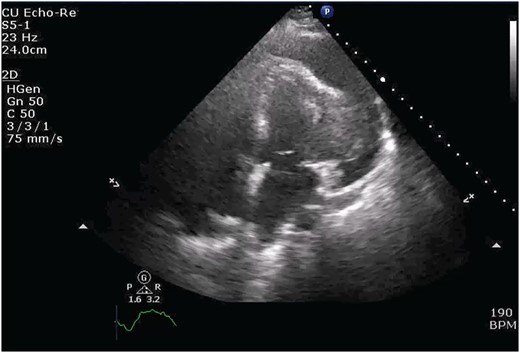

Chest X-ray found an enlarged cardiomediastinal silhouette with mild pulmonary edema (Fig. 1). A computed tomography angiography (CTA) of the chest to rule out pulmonary embolism (PE) was ordered. After the patient returned from imaging, she was found to have a heart rate of 178. Patient was awake, did not appear to be in any more distress and remained hemodynamically stable. Repeated ECG showed monomorphic ventricular tachycardia, with the patient remaining non-distressed. Patient was started on i.v. amiodarone, and urgent cardiology consult was obtained. A transthoracic echocardiogram depicted a large mass measuring 5 cm by 7 cm occupying the basal and mid portion of the anterior and lateral walls of the left ventricles with large pericardial effusion located at the lateral posterior wall of the heart, findings suggestive of impending tamponade (Fig. 2). CTA of the chest reported no acute PE with a large mass (10.5 × 7.5 × 9.5 cm3) occupying the anterior wall of the left ventricle and extending to the pulmonary outflow tract (Fig. 3).

Large ventricular mass measuring 10.5 × 7.5 × 9.5 cm3 invading epicardium and myocardium.